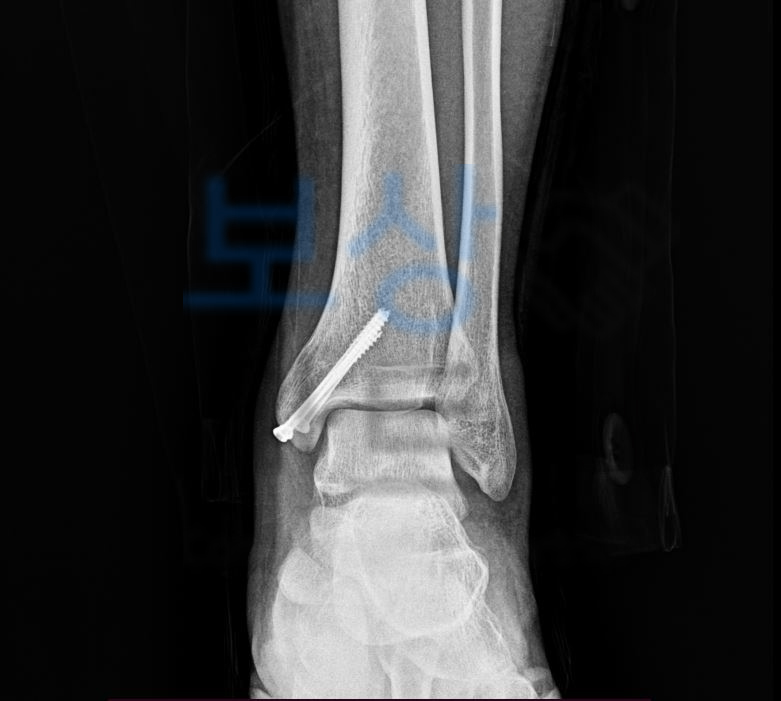

수술 후 사진도 함께 보시죠. 먼저,** 산재보험**과 일반 생손보험에서 보상가능합니다. 저희 보상파트너는 산재사고를 당한 재해자의

장해급여 청구를 도와드리고 있습니다.